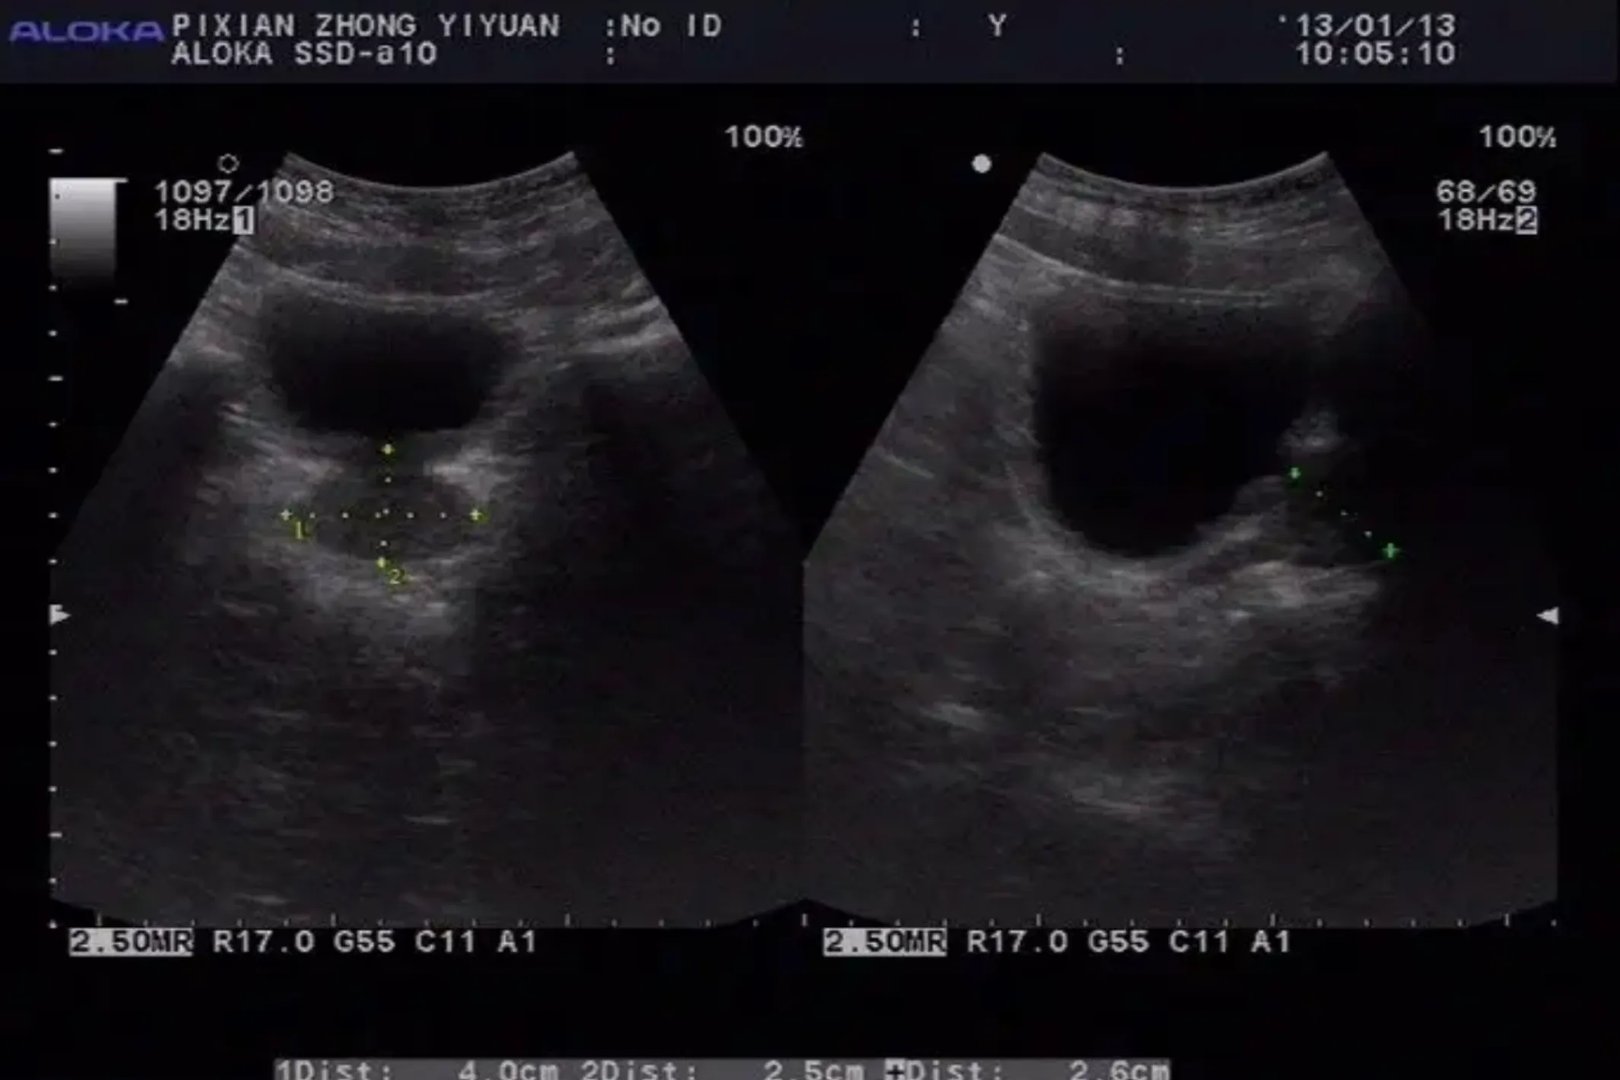

的有关信息介绍如下:彩超是彩色多普勒超声的简称,可对血管、腹腔脏器、心脏、子宫及附件、小器官、前列腺及精囊等全身性脏器进行检查。